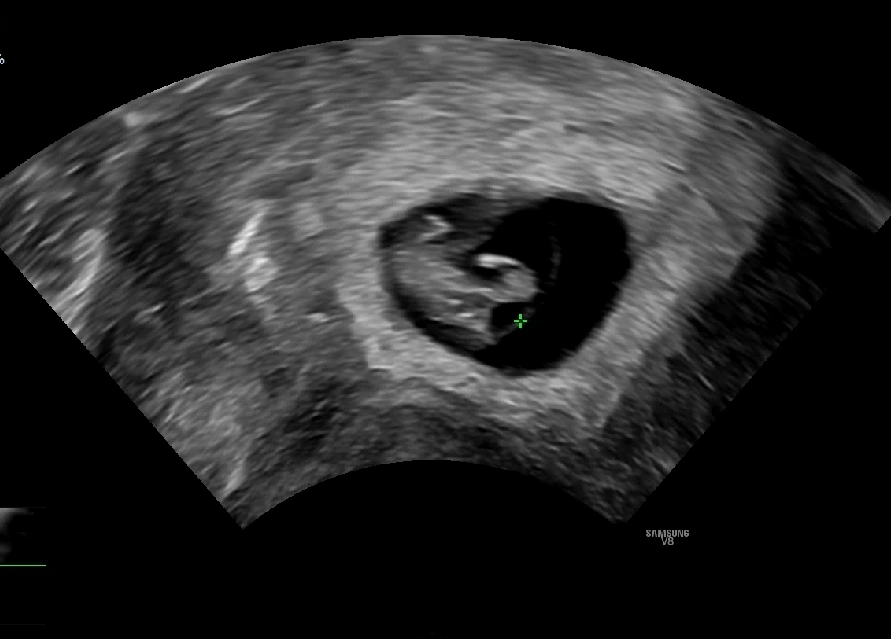

오빠와 사이좋게 손잡고 병원에 갔다. 오늘은 아기의 심장소리를 들을 수 있다고 선생님께서 말씀하셨다. 지난 번에 작은 점이었던 아기였는데, 오늘은 무언가 많은 것들이 생겼다 (?) #임신7주차초음파 아직 사람의 형태를 갖추고 있지는 않지만 꼬리같은 것도 보이고, 외계인 같기도 하다. (ㅎㅎㅎ)

남편이랑 나는 심장소리를 듣고 너무너무 신기했는데 동시에 너무도 얼떨떨했다. 심장 소리를 들을 때 살짝 울컥하긴 했는데 스멀스멀 올라고 있는 입덧으로 나는 기운이 많이 떨어진 상태였고, 평소에 입던 바지가 답답해서 배가 조여오는 불편함 등으로 컨디션이 좋지 않았다. 우리 서로 아기 심장소리를 듣고 마음은 참 기뻤는데 내가 컨디션이 안좋아서 남편도 나를 걱정하느랴 아기에 대한 기쁨을 온전히 느끼지 못했다.

임신7주차 초음파 & 심장소리